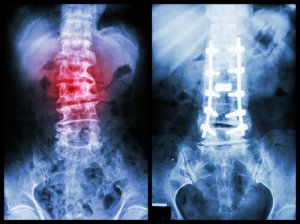

• Спондилодез. Целью этой операции является создание прочной связи между позвоночными сегментами, чтобы стабилизировать позвоночник. Основная идея заключается в том, чтобы соединить повреждённые позвонки таким образом, чтобы они стали единым целым. Для этого израильские хирурги используют высококачественные ортопедические устройства (винты и стержни), а также костные трансплантаты или их аналоги.